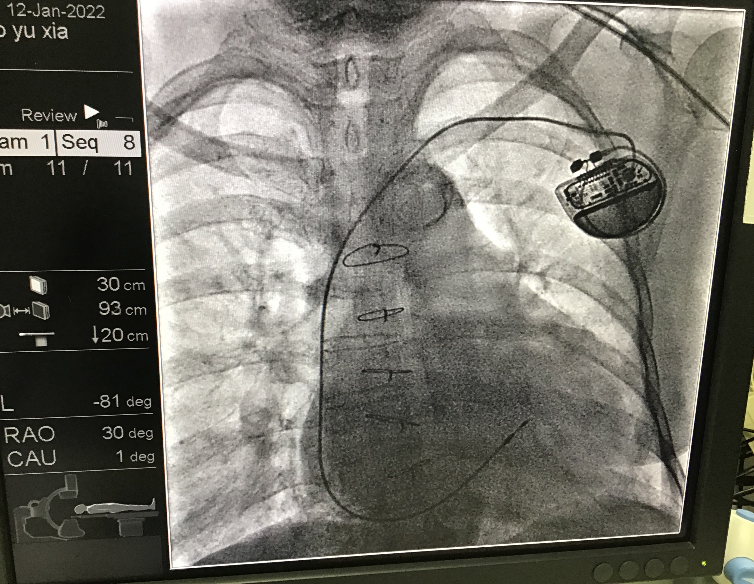

心内科团队详细讨论患者病情后,制定了周密的手术计划。1月12日上午,在心血管病院郑强荪院长组织和指导下,薛嘉虹副主任医师、万招飞副研究员、张春艳主治医师及主管护师鲁红娥、护师王军的组成的介入团队为患者实施了心脏起搏器植入术。

心脏起搏器对无菌要求严格,而且需要精细的手术操作。肥大的防护服,雾气满屏的防护罩,防护服外边还得穿上30余斤重的铅衣,最外面是手术衣。大白就像穿上了铠甲,为术者操作带来了诸多不便。且患者30年前曾接受过心脏外科开胸手术,由于时间久远,家属无法告知当时的病因及手术详情,术前床旁心脏彩超显示全心扩大,多个瓣膜存在中到大量反流,扩大的心脏以及外科手术瘢痕对心脏结构的牵拉,使正常的心脏结构发生了异常变化,这对起搏器心室电极的植入带来了巨大的困难。

然而,该患者目前已经发生心衰,并且预测起搏器植入后心室起搏比例高,如果选择相对容易的位置植入电极,长时间高比例的起搏会影响患者预后。为了让患者获得更好的长远预后,郑强荪院长精益求精,经过反复尝试,最终团队顺利将心室电极植入患者右心室高位间隔,术中各项参数测试完美,起搏阈值低于0.5mv。术后患者高兴得夸赞,“你们技术太高了,突然间我感觉身体轻盈了,气顺了,精神头大了,而且手术一点都不痛!”